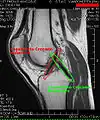

MRI

Both anterior cruciate ligament (ACL) and posterior cruciate ligaments (PCL) are hypointense on both T1 and T2 weighted images of MRI. However, some high signal striations are often seen at the distal part of the ACL, making ACL higher intensity than PCL on MRI scans.[20]

Knee MRI (PD TSE FS sagittal)

Knee MRI (T1 TSE sagittal)- Knee MRI (sagittal TSE FS)